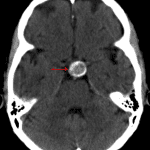

CT

- Calcified suprasellar mass